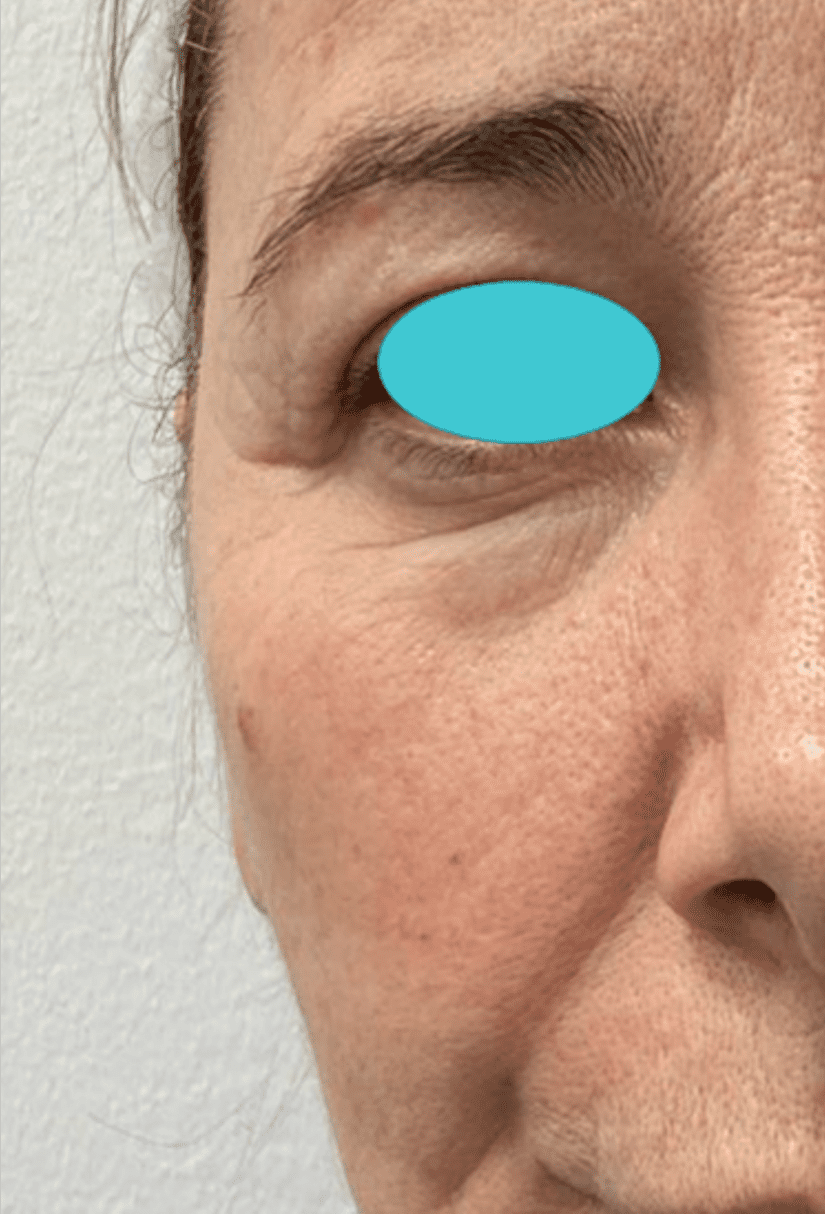

Eye Bag, Dark Circles & Tear Trough

Before

After